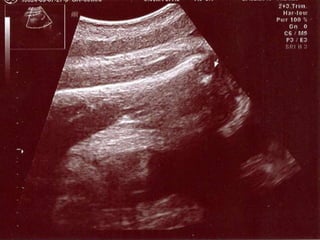

FL

 En kolay ölçüm

 Tüm kemik ölçülmez

 Transduser diafizin uzun eksenine paralel

 Femur başı ve distal kondil görülür